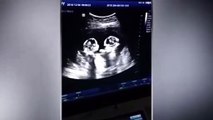

Anne karnındaki bebeğe operasyon İdrar yollarında tıkanıklık bulunan anne karnındaki bebeğe şant takıldı 3 kez düşük yaptıktan sonra yeniden gebe kalan anne adayının, idrar yollarında tıkanıklık bulunduğu tespit edilen 4 aylık bebeğine anne karnındayken müdahale yapıldı MCBÜ Hafsa Sultan...

İdrar yollarında tıkanıklık bulunan anne karnındaki bebeğe şant takıldı

3 kez düşük yaptıktan sonra yeniden gebe kalan anne adayının, idrar yollarında tıkanıklık bulunduğu tespit edilen 4 aylık bebeğine anne karnındayken müdahale yapıldı

MCBÜ Hafsa Sultan Hastanesi Perinatoloji Bölümü Bilim Dalı Başkanı Prof. Dr. Faik Mümtaz Koyuncu:

"Değerlendirmemizde bebeğin alt idrar yollarında tıkanıklık tespit ettik. Bundan sonra idrarının yapamadığı takdirde böbrekleri çalışmamaya başlayacak ve bebek idrarının yapamamaktan eks olacaktı"